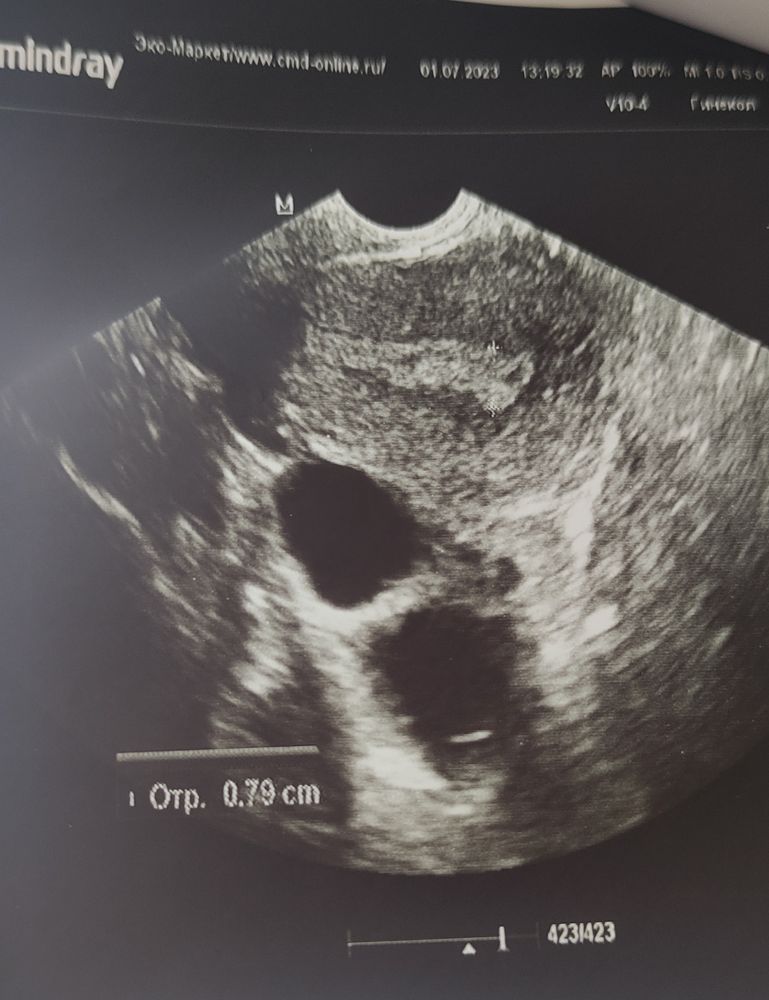

А вот фото кисты и какого-то образования

Врач сказала, что это может быть как начало образования полипа эндометрия, так и повреждением после выскабливания (было 20 лет назад). Раньше такого никто на УЗИ не наблюдал и ничего не говорил, так что больше склоняюсь к первому варианту из предложенных.

Что за вид кисты не сказала, но уточнила, что либо две, либо одна с перегородкой, точно нельзя определить. Раньше никогда кист не было, хотя может я просто не попадала на УЗИ с ними. Назначила сделать УЗИ на 5-9 ДЦ после М, что бы посмотреть структуру эндометрия и состояние кисты.